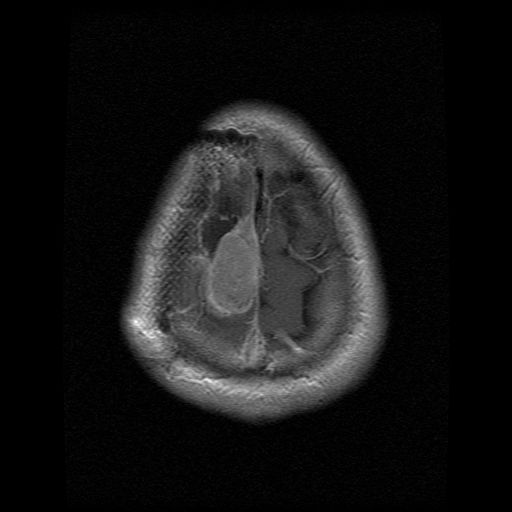

On Monday the report told me what I already knew.  The mass had grown bigger by half a cm all around [top view, ear-to-ear view] in one month.  The radiologist no longer considered it an abscess, but said it was tumor re-growth.  When Dr. Black saw the films he agreed it was tumor, but thought radiation was the next course of action, not surgery.  He seemed a little surprised that I was not doing radiation already.